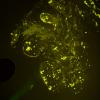

1C1 Amyloid (Case 1) Thio-S Image_01 - Copy

1C2 Amyloid (Case 1) Thio-S Image_03 - Copy